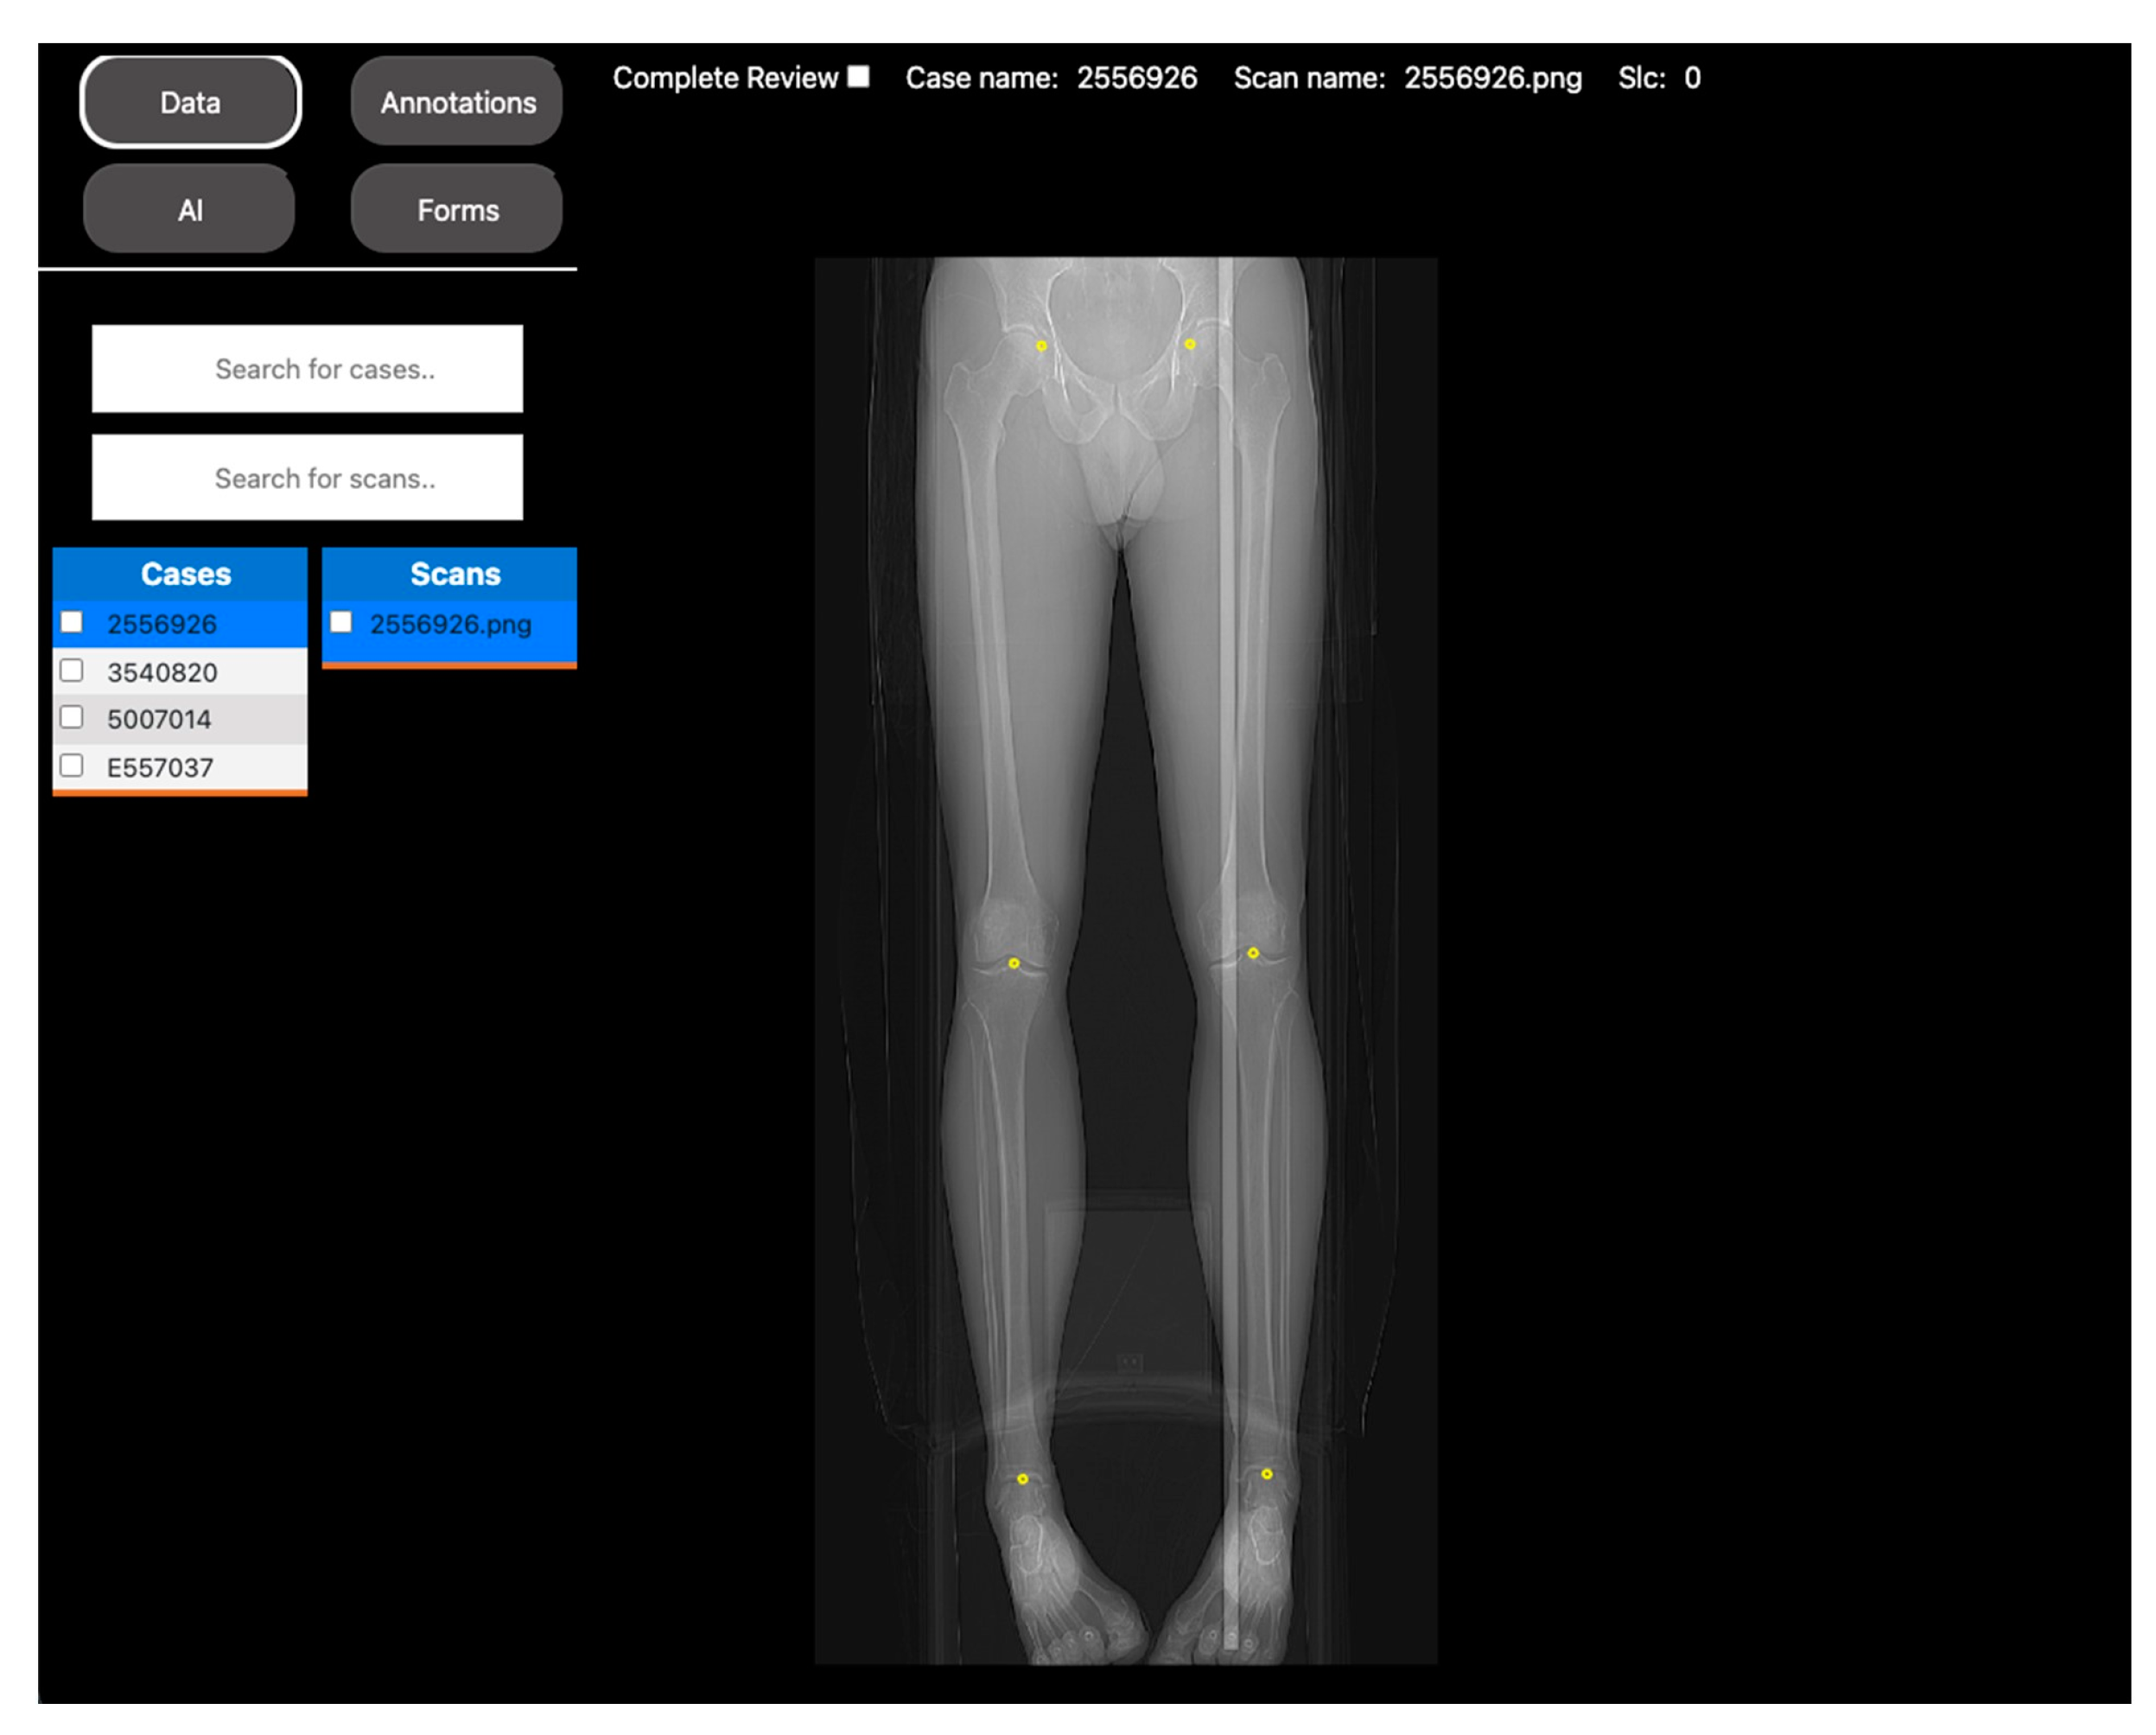

2.1.2. Automated Measurements of Leg Length on Radiographs by Deep Learning

| Objective | Assess the diagnostic image quality of a novel MRI sequence to image the lungs (see Figure 1). | Develop a DL model to automatically identify anatomical landmarks in full leg radiographs (see Figure 2). |

| Methodology | Three radiologists assessed the diagnostic image quality of a group of post-COVID-19 patients who underwent both an MRI and a CT scan of the lungs. | A radiologist annotated three anatomical landmarks in a cohort of full-length radiographs. |

| DV project set up | Each patient’s MRI and CT images, along with the diagnostic quality metrics for scoring, were incorporated into a DV project. Access to the project was then provided to the three radiologists to review the images. | The training set of the cohort was located into a DV project, along with the points annotation tool. Access was given to the radiologist to annotate the images. |

| Results | The scores were extracted from the platform as a CSV file for statistical analysis. | The coordinates of the annotations were extracted as a CSV file to use as the ground truth for DL model training. |